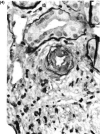

FIG. 5

The interlobular artery shown has fibrin deposition, lymphocytes, and nuclear debris in its media. The renal function tests in the patients improved as the dosage of FK506 was lowered.